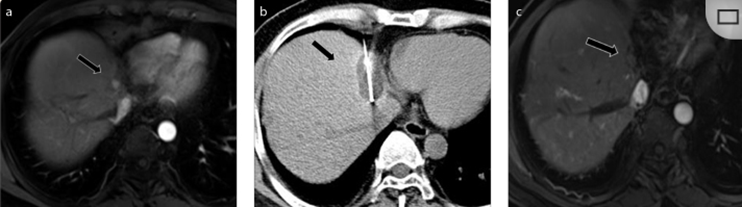

(A)动脉期CT图像显示有一个包膜下结节(箭头)。(C) 在手术过程中的CT显示一个冷冻探针位于病灶内。随访时间中位数为7个月(范围:3-12个月),随访期间患者无局部肿瘤进展或死亡。

(A)门静脉期 CT 图像显示胆囊附近有病变(箭头)。(D)消融手术后 1 个月CT 显示完全消融。